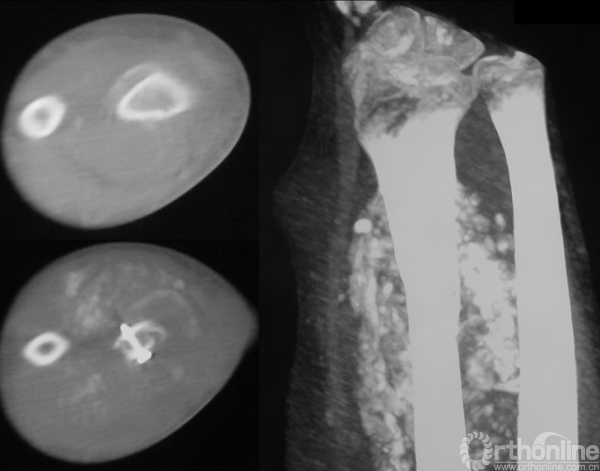

男性,16岁。患者入院3个月前摔伤右前臂,即出现疼痛、肿胀、活动受限。

图14-1 伤后X线平片正侧位

1.有外伤病史,但无骨折前局部疼痛等症状。而是在低暴力创伤的情况下出现骨折,可能并非单纯创伤暴力所致。

2.X线平片显示右桡骨干骨皮质不连续,骨折端内可见边界不清之溶骨破坏,其内密度不均,应该首先考虑为病理骨折,但又未见明确的骨膜反应和软组织包块。所以应继续进行检查,包括细致的影像学检查如局部加强CT来判断是否确为病理骨折、是否有皮质破坏及软组织包块。